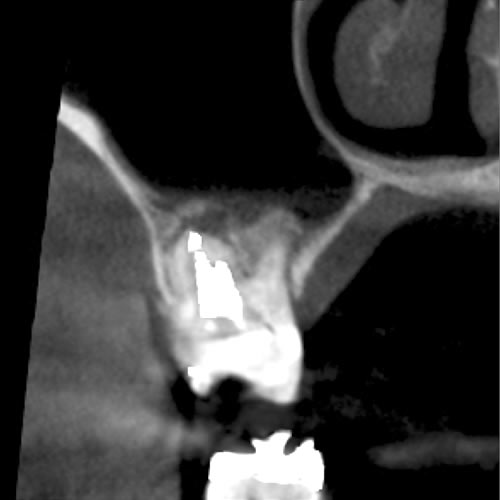

CT画像を見ると根管が2本あることが分かりました。(レントゲンだけでは分かりませんでした。)

| 治療説明 | 右下第2小臼歯、他院で根管治療した後に頬側根尖部から排膿があます。X線CT画像では、根管が2本あり、そのうち舌側が根管充填されていませんでした。顕微鏡下で2根管とも根管充填処置を行い、4ヶ月で、X線透過像は消失しました。 |

|---|---|

| 治療期間 | 6〜24ヶ月 |

| 治療費用 | 150,000〜300,000円 |

| 治療に伴うリスク | 根管内からの治療で根尖病巣が治らない場合は、外科的に根尖病巣を除去する必要があります。 再根管治療を繰り返す場合、歯根の厚みが薄くなり、歯根破折のリスクが高まります。 |